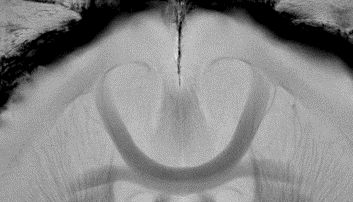

BioSpec 180/11 是当前行业领先的超高场强磁共振成像系统,其出色的高灵敏度可实现高分辨率。流线型设计专为小鼠研究优化,操作简便,而强大的软件则确保获得出色的成像效果。配备MRI CryoProbe可进一步提升灵敏度,配合高达1000 mT/m的梯度强度,实现极高分辨率成像。该设备采用超屏蔽制冷(USR)磁体技术,有效降低维护成本并延长保养周期。

• 原生梯度强度达740 mT/m,可升级至1000 mT/m,呈现清晰高分辨率图像

出色的高分辨率,梯度强度高达1000 mT/m